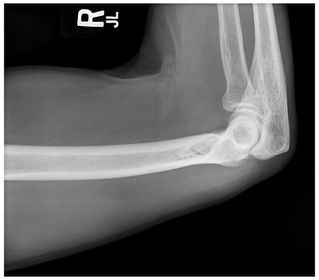

Which projection/position is this? PA Lateral Humerus

Projection/position? Lateral Humerus